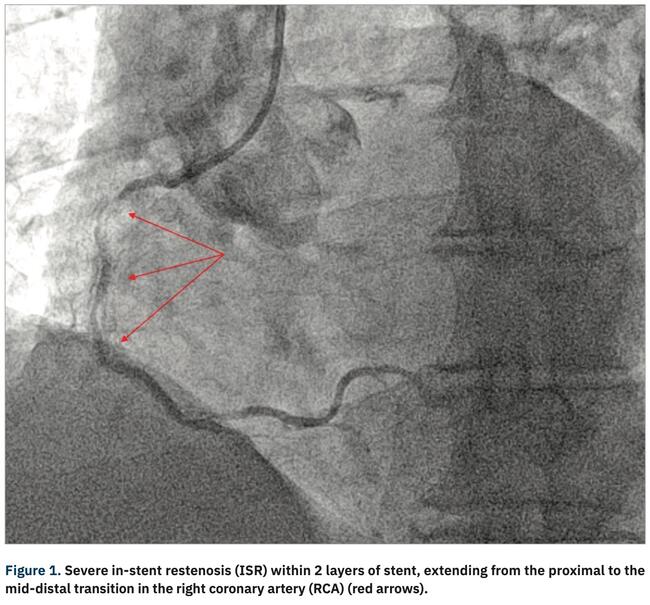

Orbital Atherectomy Crown Interaction Resulting in Partial Stent Explantation During Management of In-Stent Restenosis

In-stent restenosis (ISR) is the Achilles’ heel of percutaneous coronary intervention (PCI). A common cause of ISR is an under-expanded stent secondary to under preparation of a target vessel with circumferential deep calcification. ISR management is challenging and there are several treatment modalities currently available, including drug-eluting stents/balloons, cutting/scoring balloons, atherectomy, and intravascular brachytherapy.1-4 Orbital atherectomy (Cardiovascular Systems, Inc. [CSI]) has limited evidence in the management of ISR.5 A recent retrospective series of 41 patients with undilatable under-expanded stents demonstrated a 98% success rate for orbital atherectomy with a 5% rate of periprocedural myocardial infarction/Ellis type II coronary perforation.5 We describe a case of orbital atherectomy crown entrapment during atherectomy of multilayer in-stent restenosis, resulting in segmental stent explantation.